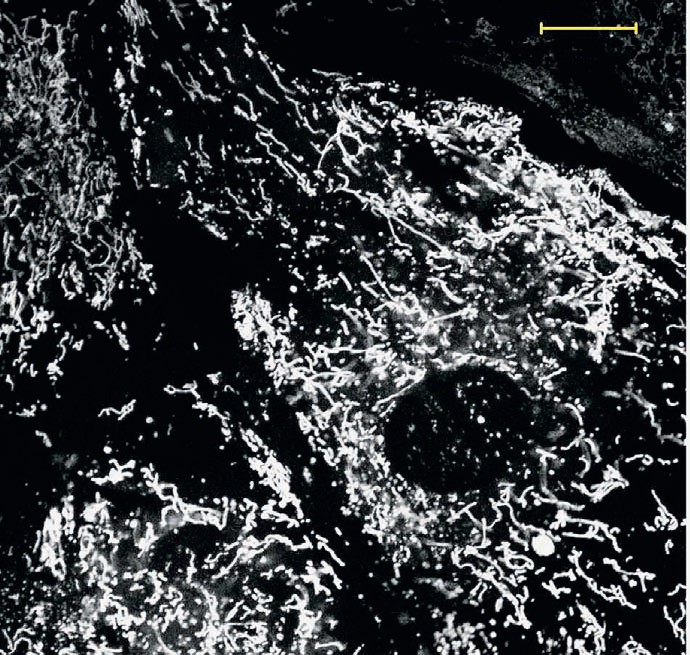

Сотрудники МГУ им. М. В. Ломоносова для лечения почечной недостаточности новорождённых испытали антиоксидант SkQR1. Сепсис у новорождённых крысят моделировали с помощью инъекции липополисахарида клеточной стенки бактерий. Вооружившись электронным микроскопом, исследователи обнаружили, что основные структуры, страдающие при действии липополисахарида, — митохондрии. Главная функция этих органелл клетки — окисление органических соединений и использование освобождающейся при их распаде энергии для генерации электрического потенциала, синтеза АТФ и выработки тепла (термогенеза). В экспериментах заметное нарушение тонкой структуры митохондрий наблюдалось уже через три часа после инъекции и достигало максимума через сутки. Одновременно в моче обнаруживалось и значительное повышение маркеров острой почечной недостаточности.

Повреждение митохондрий приводит к высвобождению активных форм кислорода — токсичных соединений, образующихся в биохимическом цикле окисления органики. Их выброс приводит к повреждению клетки. Исследователи попробовали вводить подопытным животным митохондриально-адресованный антиоксидант SkQR1, разработанный ранее в МГУ. Предыдущие исследования показали, что этот антиоксидант способствует заживлению ран при диабете, стимулирует рост растений, обладает антибактериальными свойствами.